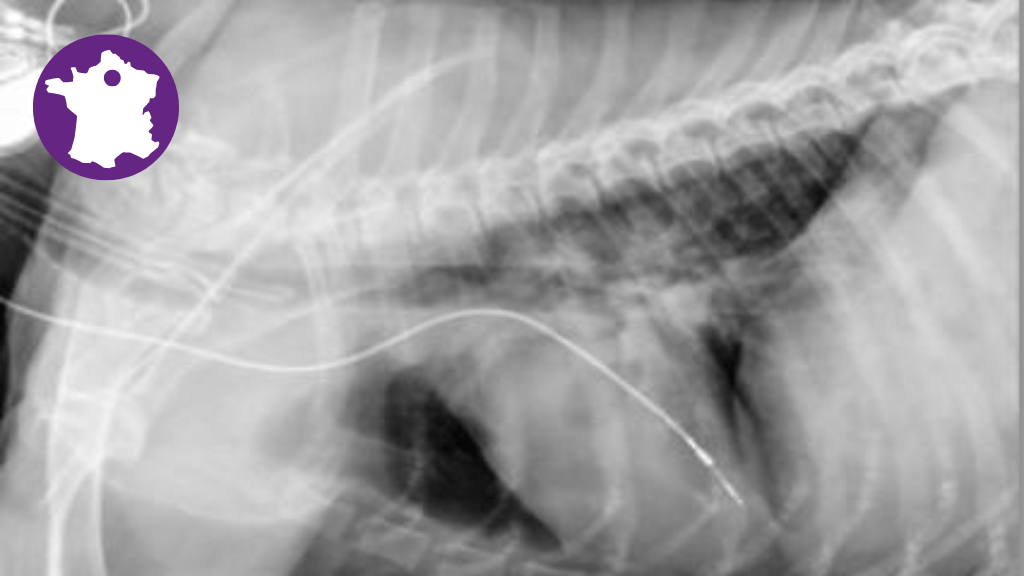

Bannière visuelle de présentation de la formation

Focus sur traitements des troubles du rythme : antiarythmiques, pacemaker, ablations. Cours d’experts, Holter pas à pas, démo pacemaker & pratiques guidées. Objectif : maîtriser stratégies pharmacologiques et interventionnelles adaptées au cas clinique.